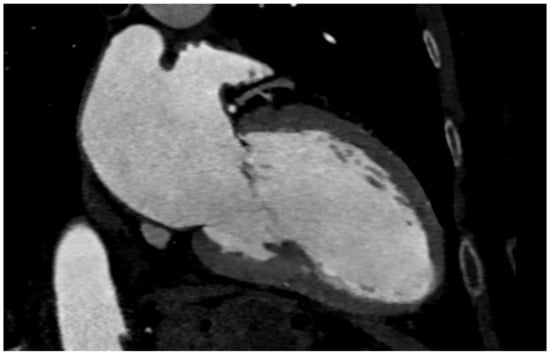

The accuracy of MDCT imaging of the sinotubular junction depends on the measurement method. Compared with axial methods, double-oblique imaging yields similar findings to planimetry, and measurements obtained by double-oblique imaging are generally smaller, as was demonstrated in a study of patients with thoracic aortic aneurysms [54]. The height of the sinotubular junction should be measured perpendicular to the ring’s plane using an electronic caliper from the annulus to its lowest point [24] (Figure 7a,b).

Figure 7.

(a) Sinotubular junction and (b) proximal ascending aorta evaluated by CT for TAVI.